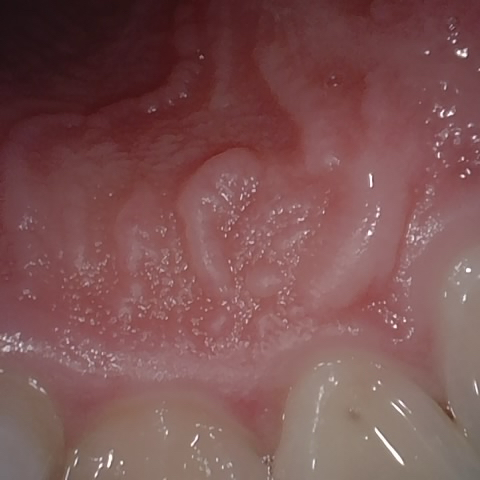

NHD39990

Annotated as "Good"